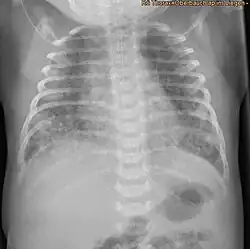

Durch das eingeatmete Mekonium entstehen in der Lunge des Kindes Bereiche mit unzureichender Belüftung (Atelektasen), während andere Bereiche dagegen überdehnt bzw. überbläht (Lungenemphysem) werden. Bei der Überblähung wirkt das in den Atemwegen befindliche zähe Mekonium wie ein Ventil. Atemgas wird bei der Überdruckbeatmung zwar am Mekonium vorbei in die nachgeschalteten Lungenbläschen eingeblasen, kann aber bei der Ausatmung nicht mehr am Mekonium vorbei entweichen und verbleibt in der Lunge. Die betroffenen Lungenbezirke können nicht mehr ausreichend ausatmen und werden so überbläht. Die Folgen eines solchen ungleichmäßigen Belüftungsverhaltens einzelner Lungenbereiche sind in der Röntgenaufnahme der Lunge (Röntgen-Thorax) deutlich zu sehen. Der Radiologe befundet ein „Mischbild aus diffuser Minderbelüftung (Atelektasen) bei gleichzeitig vorhandenen Bereichen der Überblähung (Emphysem)“. Sehr häufig tritt in einer solchen Situation ein Pneumothorax auf. Die sehr dünne Membran der überdehnten Lungenbläschen zerreißt und Atemgas gelangt dann aus den Alveolen in das Lungen-Bindegewebe (interstitielles Emphysem). Findet diese außerhalb der Alveolen gelegene Gasansammlung dann Anschluss an den Pleuraspalt, wird dort die Haftung der beiden Pleurablätter aufgehoben und die Lunge zieht sich auf Grund der Eigenelastizität zusammen. Hierdurch kann eine akut lebensbedrohliche Situation für das Kind resultieren. Als weitere Komplikation der Mekoniumansammlung in den Atemwegen entsteht eine reaktive Pneumonie (Lungenentzündung) und eine Inaktivierung von lungenstabilisierendem Faktor (Surfactant). Während bis vor 15–20 Jahren ein MAS noch eine schwer zu behandelnde Erkrankung des Neugeborenen mit hoher Sterblichkeit darstellte, sind die Behandlungsergebnisse des MAS heute durch spezielle Beatmungstechniken, antibiotische Therapie, inhalative Stickoxidtherapie (iNO) und vor allem der Gabe von aus Tierlungen extrahiertem lungenstabilisierendem Faktor (Surfactantsubstitution) erheblich verbessert worden. So ist der ECMO-Bedarf bei Neugeborenen mit diesem Krankheitsbild über die letzten 10 Jahre kontinuierlich gesunken.[6]